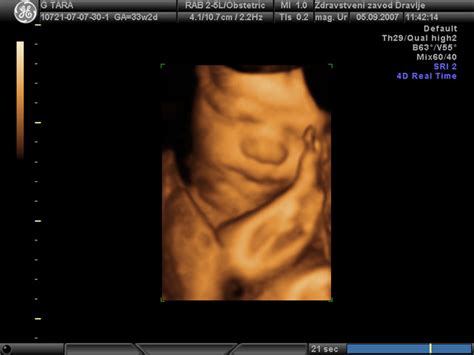

Pregled v 20. tednu nosečnosti: Ta ključna preiskava se opravi med 20. in 24. tednom. Zaradi zagotovitve dovolj časa za morebitne dodatne preiskave, se v nekaterih ordinacijah opravi takoj po dopolnjenem 20. tednu. Preverijo se lega in rast ploda (merjenje premera in obsega glave, obsega trebuha in dolžine stegnenic). Sledi natančen pregled zunanjosti in notranjih organov ploda, vključno z obliko glave, ocenjevanjem možganskih struktur, obraza (razdalja med očmi, očesne leče, izključitev zajčje ustnice), hrbtenice (s 3D preiskavo za potrditev pravilne oblike in zaprtosti), organov v prsnem košu in trebušni votlini. Posebej zahteven je pregled srca, ki je odvisen od položaja ploda, debeline trebušne stene nosečnice in položaja posteljice. Pregledajo se tudi prepona, velikost in oblika želodca, ledvičke, sečni mehur in sprednja trebušna stena. Preverijo se položaj prstkov na rokah in stopalih. Ginekolog ocenjuje tudi položaj posteljice, število žil v popkovnici in količino plodovnice. Med tem pregledom se izključujejo "mehki" (blagi) in "trdi" (močni) označevalci, ki bi lahko nakazovali na kromosomsko napako ploda.